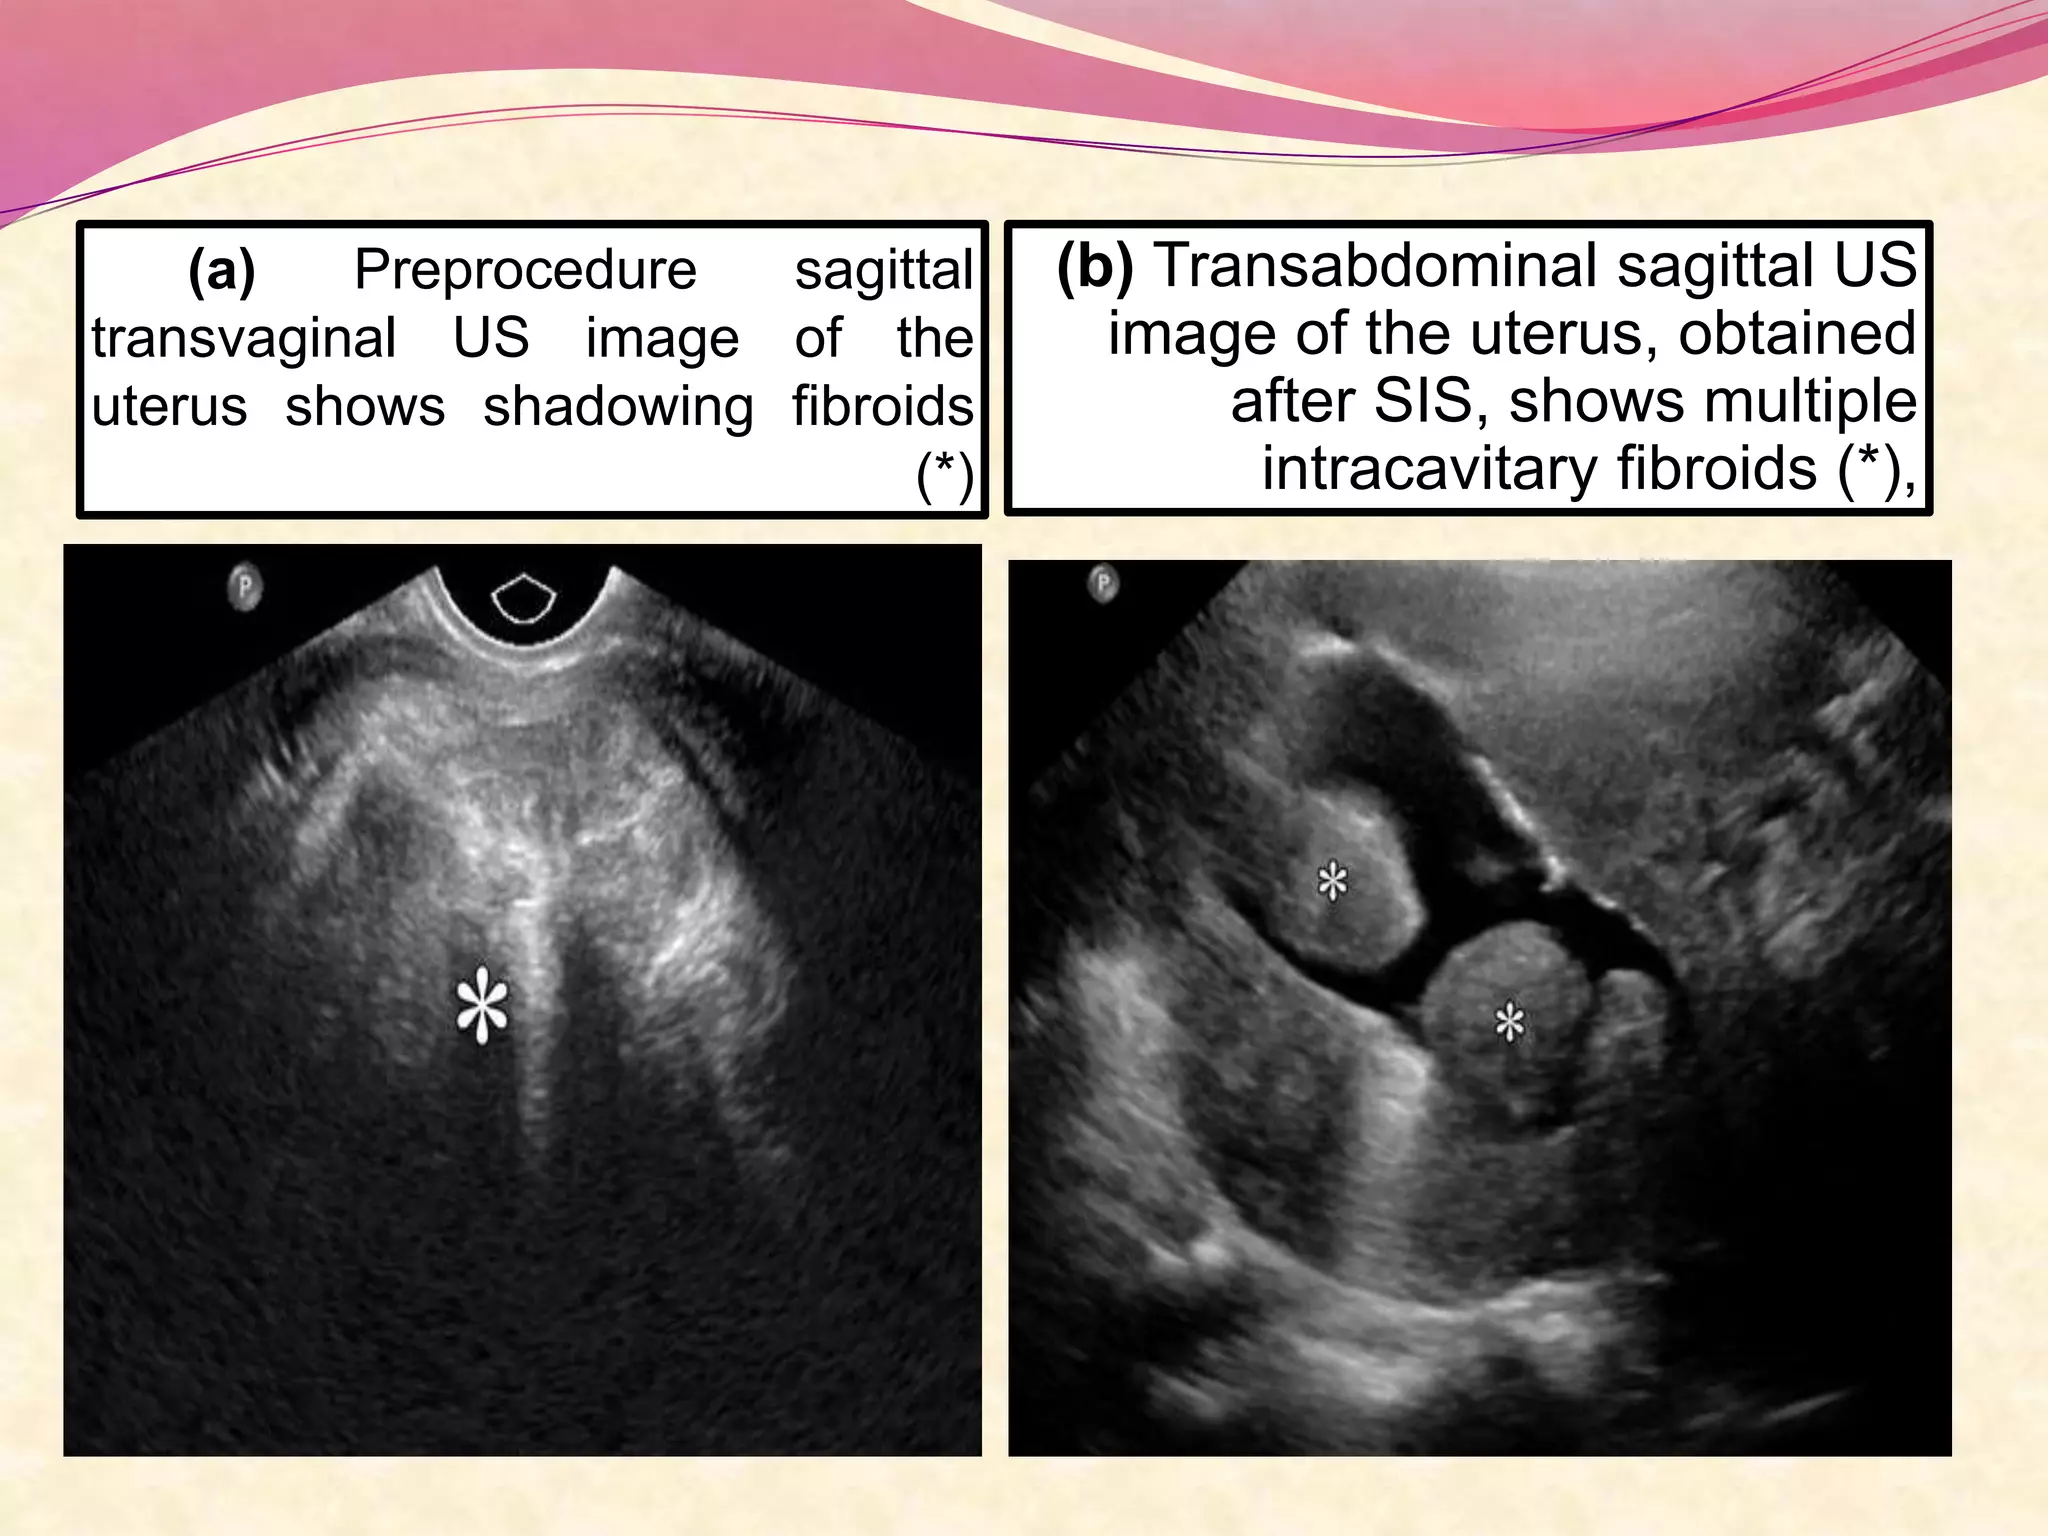

(a) Preprocedure sagittal

transvaginal US image of the

uterus shows shadowing fibroids

(*)

(b) Transabdominal sagittal US

image of the uterus, obtained

after SIS, shows multiple

intracavitary fibroids (*),

(a) Preprocedure sagittal transvaginalUS image of the uterus shows shadowing fibroids (*) (b) Transabdominal sagittal US image of the uterus, obtained after SIS, shows multiple intracavitary fibroids (*),